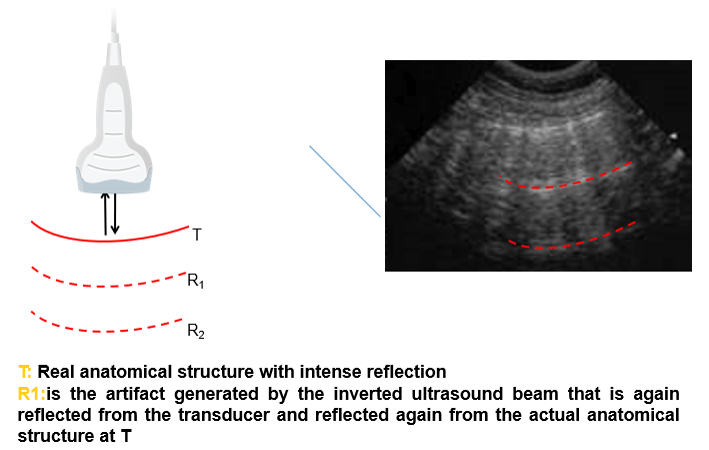

Reverberation

The third artifact is the reverberation artifact, which is related to the “trapping” of ultrasound waves between two reflective surfaces. These waves bounce between the surfaces, where at each bounce, a small echo is released to the probe and forms an image. This reverberation causes a repetitive artifact on the ultrasound image. The appearance of the reverberation artifact depends on:

- The size of the two reflective surfaces

- The distance between the two reflective surfaces (long vs short path reverberation artifacts)

- And how much ultrasound energy is dissipated or attenuated, between each re-reflection